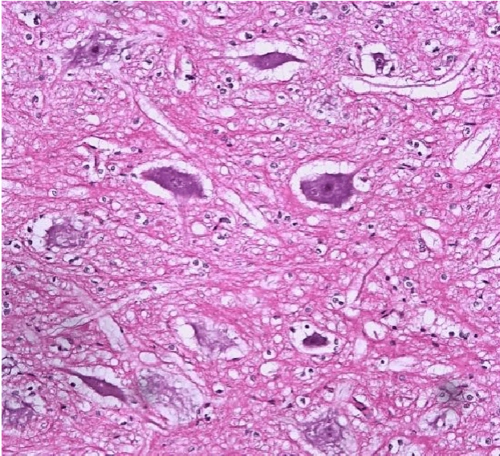

固有层内有极丰富的淋巴组织,形成许多淋巴小结,并突入粘膜下层,致使

组织切片:汗腺腺瘤

病理学组织切片